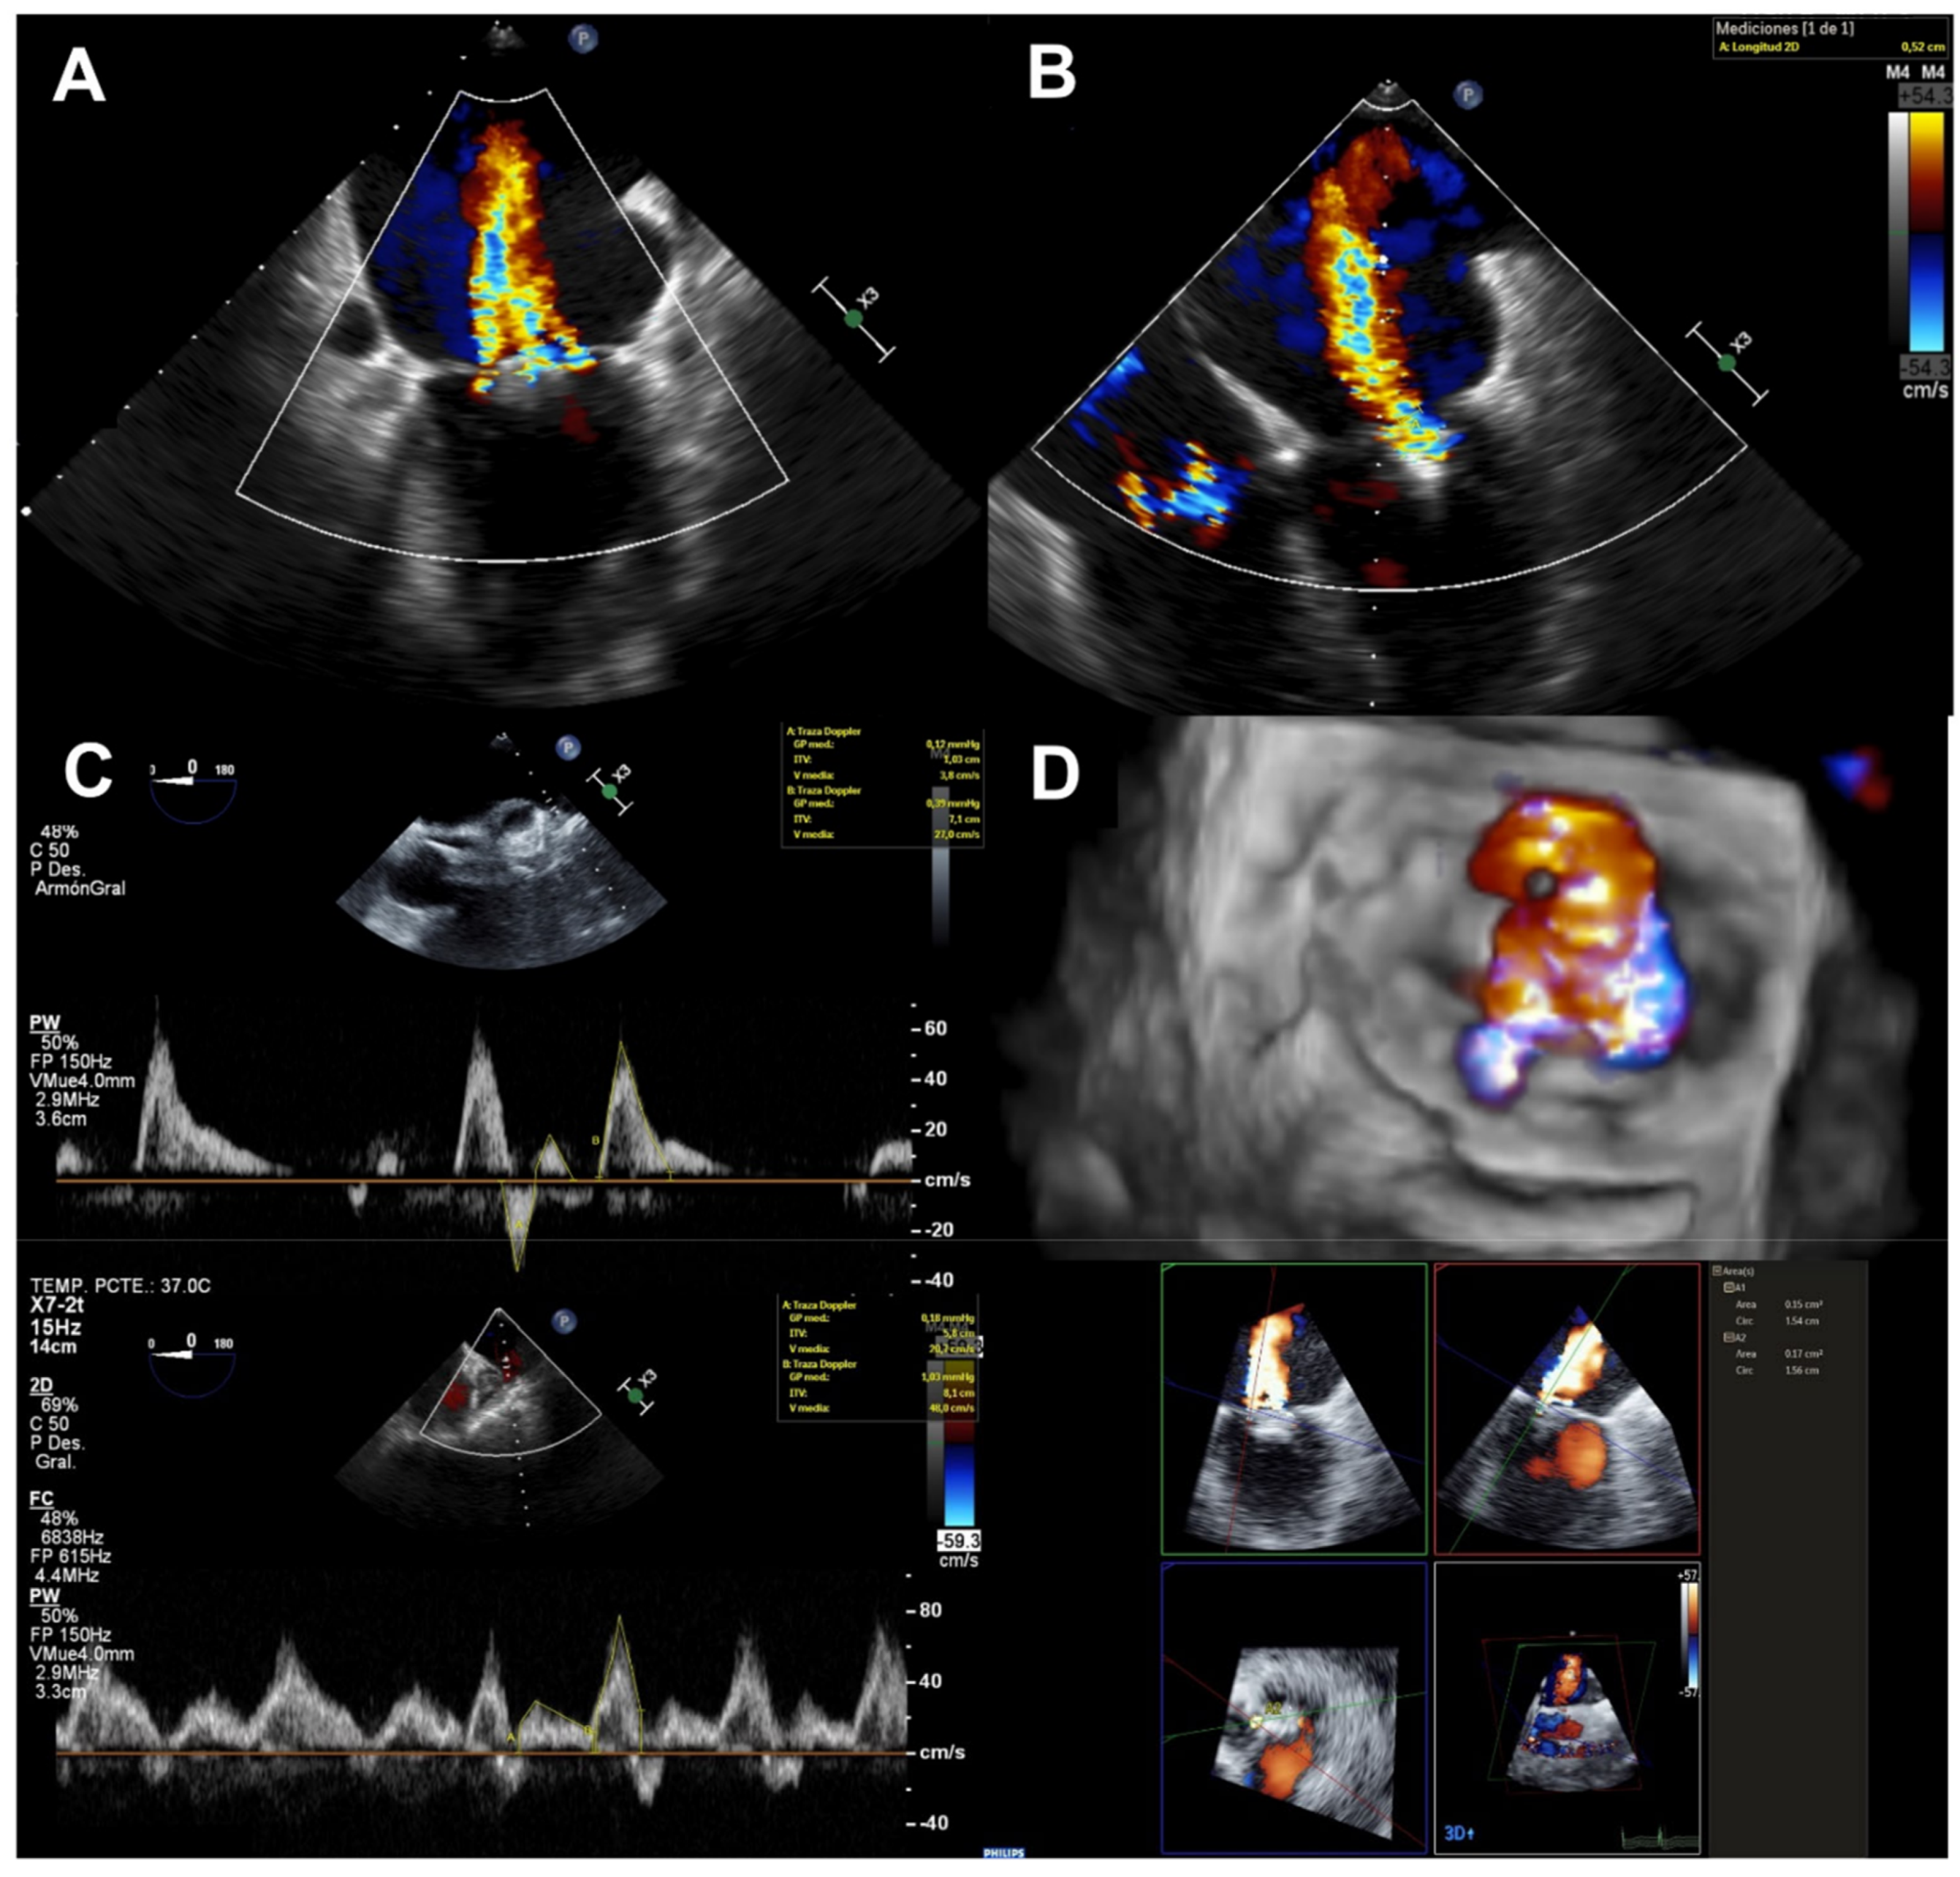

2.2. Echocardiographic Evaluation